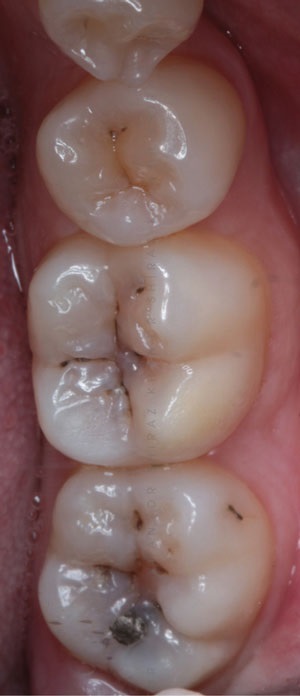

A rubber dam is used regularly for any adhesive dentistry in restorative practice; however, its use is compounded when removing amalgam. It has been shown that the mercury in amalgam restorations are held in a lattice as an alloy and therefore do not confer any health risks. When it comes to removal, some studies have found reduction in a patient’s peak levels of mercury in plasma when employing the use of rubber dam for amalgam removal.8 In most cases, therefore, a rubber dam is employed as the isolation method of choice (Fig. 2).

• Figure 2